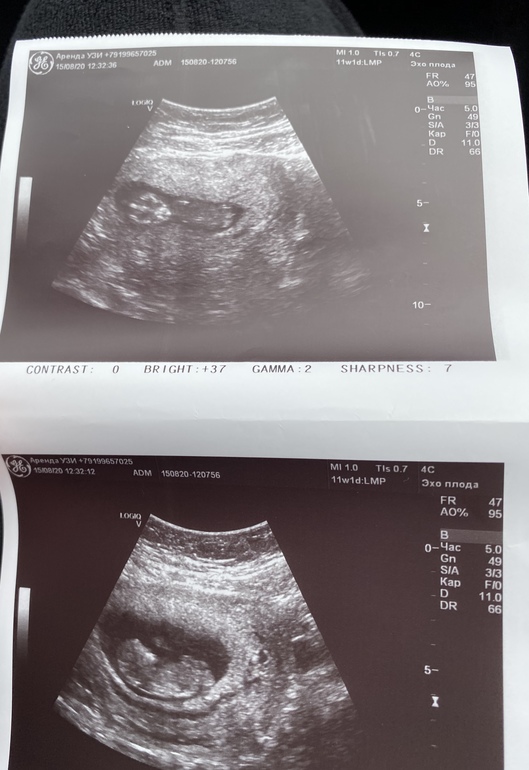

Всем привет,я так переживала а всё хорошо слава богу)малявочка КТР 52 воротниковое пространство 1,5 нос есть)пол не сказала(но я не увидела торчка никакого) может повангуем?)Бесплатный скрининг 24 августа может там скажут уже)